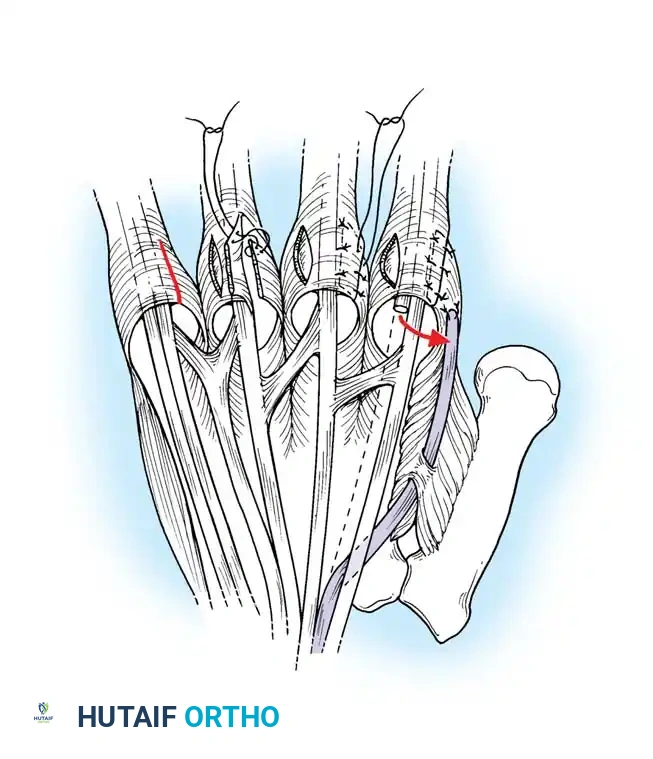

TECHNIQUE 70-1: Beckenbaugh

Tendon Preparation: Pull the FDS tendon distally and incise the decussation (Camper's chiasm), splitting the tendon into its two constituent slips. If necessary, extend the incision proximally and release adhesions at the A1 pulley level to allow adequate distal translocation of the tendon.

Splitting the FDS tendon into two slips at the level of the decussation. -

Slip Harvesting: Pull the divided FDS tendon distally and incise the ulnar slip proximally, leaving a 5-cm slip of tendon attached to its insertion on the ulnar side of the middle phalanx. Pull the slip firmly to ensure its insertion has not been compromised by erosive synovitis. (Note: In the little finger, both slips are often incised and used together because a single slip is usually too diminutive).

Pulley Fenestration: Puncture the A2 pulley 3 to 4 mm from its distal border using a scalpel or fine tenotomy scissors.

Tendon Routing: Pass a small curved hemostat through the hole distally into the sheath. Clamp the tip of the harvested FDS tendon slip and pull it proximally through the fenestration in the A2 pulley.

Tensioning and Suturing: Bring the slip of tendon distally, folding it back on itself. Adjust the tension so that the digit is held at exactly 5 to 10 degrees of flexion at the PIP joint. Suture the tendon to itself using nonabsorbable 4-0 braided sutures.

Securing the tendon slip to itself under appropriate tension.

The completed FDS tenodesis, preventing PIP hyperextension while permitting active flexion.

- Closure: Repair the cruciate pulley if feasible. Close the skin over a small drain. Apply a sterile compressive dressing supported by a dorsal blocking splint to prevent hyperextension of the PIP joints.

Pitfall: Over-tensioning the tenodesis can result in a severe, iatrogenic PIP flexion contracture exceeding 30 degrees. Ensure the joint rests at no more than 10 degrees of flexion before final suture placement.